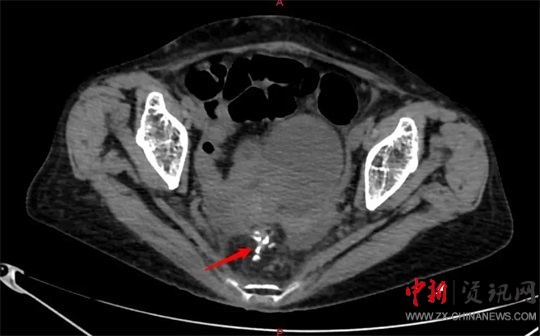

劉大勇對(duì)侯老太太進(jìn)行仔細(xì)的體格檢查及相關(guān)的影像學(xué)檢查后,考慮患者已經(jīng)急性直腸穿孔,且出現(xiàn)了血壓下降、心率增快、脈搏細(xì)弱等休克癥狀,就迅速把侯老太太的病情匯報(bào)給了胃腸外科、疝與腹壁外科主任廖新偉。當(dāng)晚8點(diǎn)左右,廖新偉立即組織科室進(jìn)行會(huì)診。大家一致認(rèn)為患者病情危重,隨時(shí)可能出現(xiàn)生命危險(xiǎn),急診手術(shù)刻不容緩。

當(dāng)晚9點(diǎn)40分,廖新偉積極協(xié)調(diào),麻醉科手術(shù)部及輸血科密切配合,以劉大勇主刀、副主任醫(yī)師汪麗偉輔助,緊急為侯老太太施行了手術(shù)。打開腹腔,驚人地發(fā)現(xiàn)侯老太太腹腔已被糞便填滿,腸子漲的像氣球那么大。術(shù)中,經(jīng)過沖洗并且減壓腸道后,醫(yī)護(hù)團(tuán)隊(duì)在直腸上段發(fā)現(xiàn)一大小約1.5cm破口,一堅(jiān)硬物嵌頓在破口處,打開腸壁,一排帶鉤的假牙映入眼前。醫(yī)護(hù)人員將假牙小心翼翼地完整取出,足足有4cm長(zhǎng)。由于侯老太太腹腔污染嚴(yán)重,且腸梗阻時(shí)間較長(zhǎng),腸壁水腫十分嚴(yán)重,無法再次重建消化道,于是胃腸外科團(tuán)隊(duì)給老太太做了直腸遠(yuǎn)端封閉+乙狀結(jié)腸造口術(shù)?紤]到患者腹腔污染術(shù)后可能出現(xiàn)感染腹腔膿腫等情況,醫(yī)護(hù)團(tuán)隊(duì)給侯老太太左右上下總共放了5根引流管。